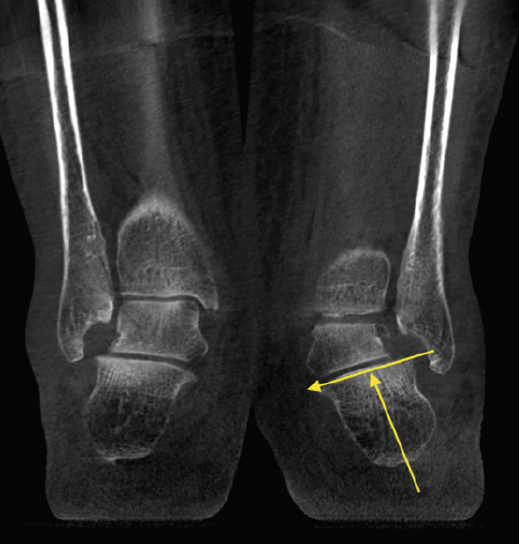

Figura 4. Estudio de la articulación subtalar bilateral.

- Patología y deformidad subtalares. Estudio de la configuración subtalar y artropatía de la misma (Figura 4).